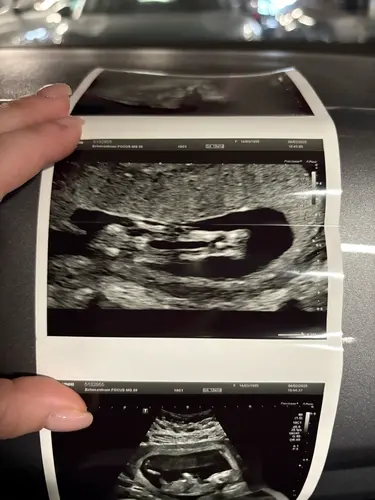

@Peterpan bij deze nog wat extra foto’s (13+5) Grappig dat Eveline een meisje denkt. Ik begrijp het ergens wel hoor. Spannend.

En deze! Had hem in het nubtopic geplaatst.

Ja bij deze is het toch duidelijk een jongen. Oeps!.💙🙈